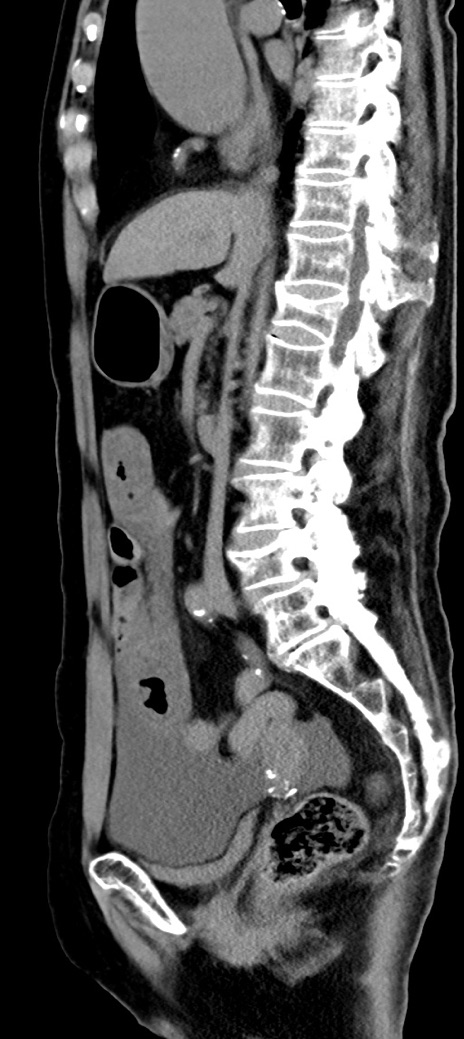

症例40(矢状断像)他院1日前

【症例】90歳代女性

【主訴】腹痛・嘔吐

【現病歴】 食欲低下、嘔吐があり昨日他院受診。肺炎と診断され入院となる。入院後より腹部全体に圧痛あり。胃管留置され経過みていたが、症状持続するため、

当院転院となる。

【既往歴】胸椎圧迫骨折、胆石症

【身体所見】腹部:中央に激痛あり、圧痛あり、反跳痛不明

【データ】WBC 17100、CRP 18.82